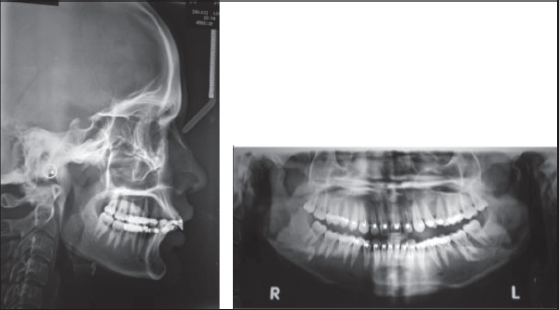

a. The skeletal stability for both Group I [Figures 35] and Group II [Figures 68] was measured at three different periods; preoperative (T1), 1-week postoperative(T2), and 6-month postoperative (T3) using a lateral cephalogram and analyzed using cephalometric analysis. The cephalometric analysis was carried out considering the following points[4] [Figure 9].

thumb

Figure 6: Preoperative lateral cephalogram and orthopantamogram-Group II

Figure 7: 1-week postoperative lateral cephalogram and orthopantamogram- Group II

Figure 8: 6-month postoperative lateral cephalogram and orthopantamogram- Group II